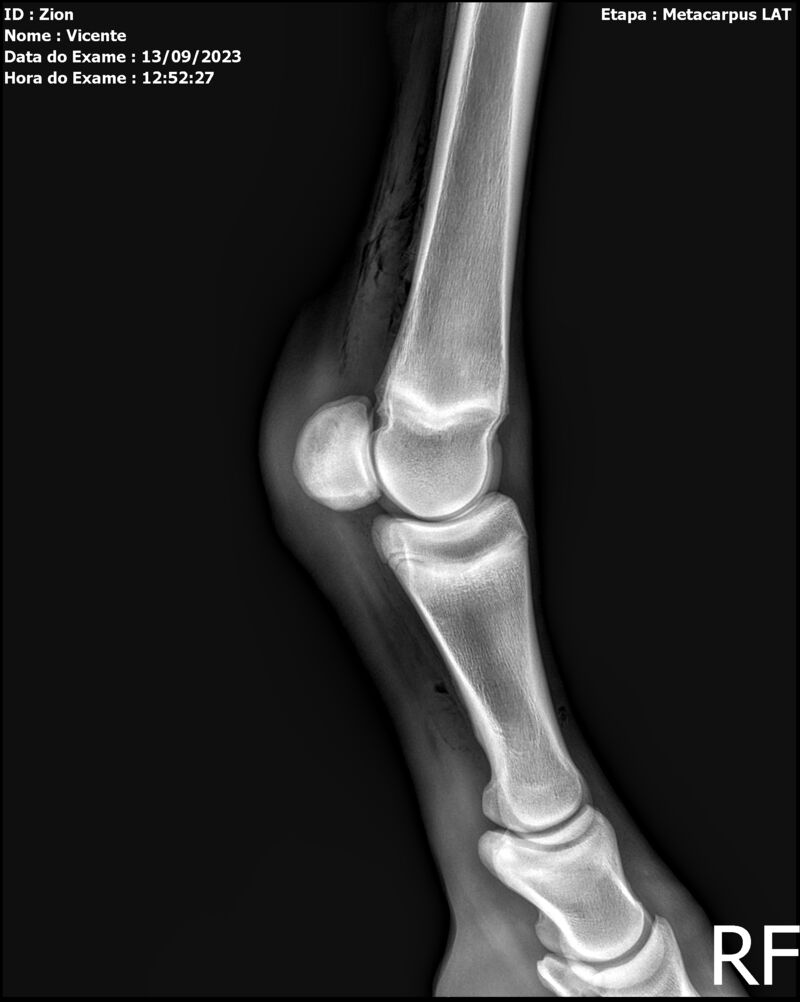

ZION ZC

Raça: BRASILEIRO DE HIPISMO

Sexo: MACHO - POTRO

Nascimento: 17/12/2022

Altura Aproximada: 1,51

Pel.: CASTANHO

Registro: EM AND

Vend.: VICENTE CONTE

Local : PORTO FELIZ/SP